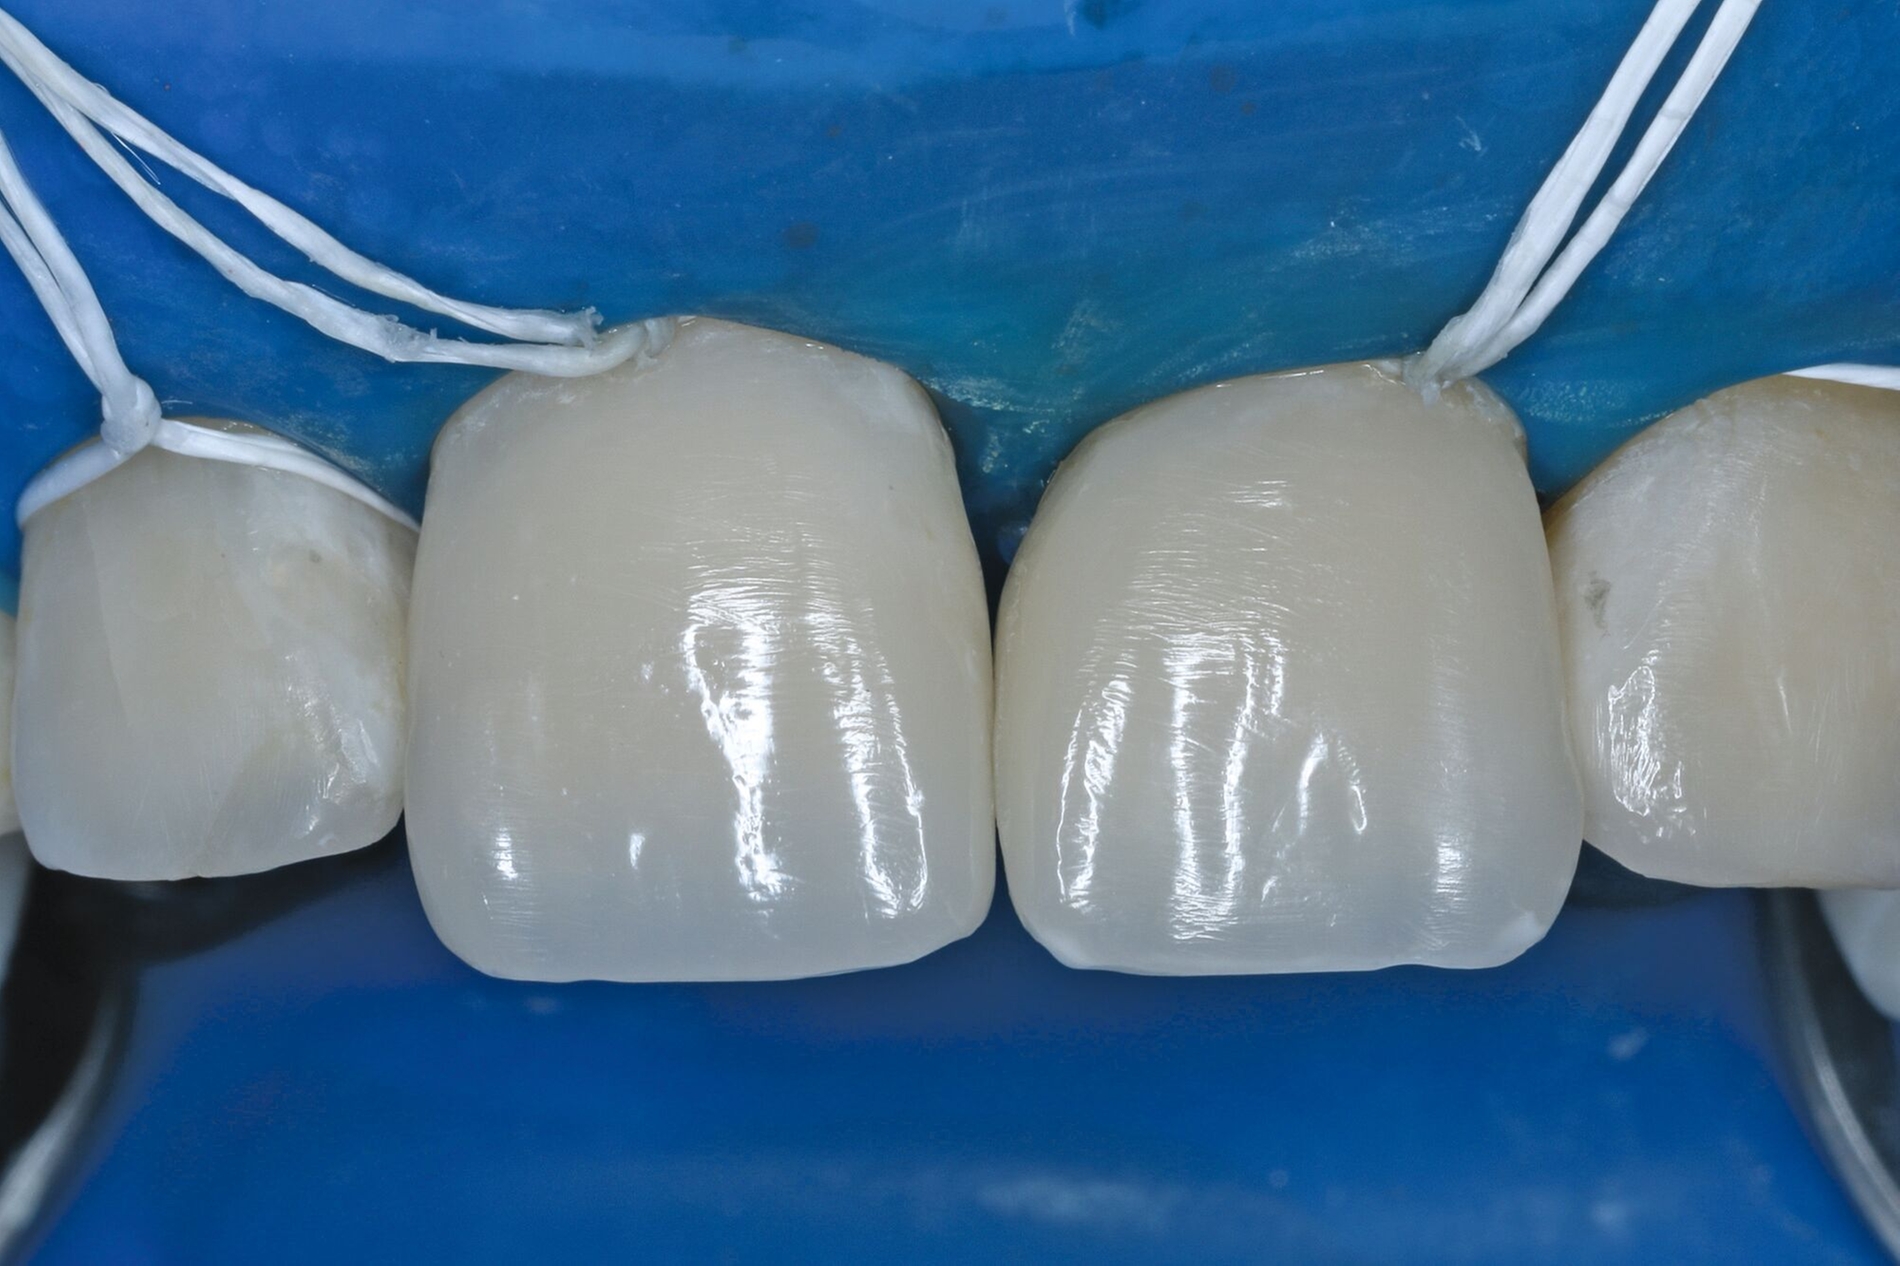

Die adhäsive Wiederbefestigung mitgebrachter Kronenfragmente bietet sich als einfache und konservative Methode zur Wiederherstellung von Funktion und Ästhetik an (Abbildung 1). Wenn das Fragment nach dem Unfall unter feuchten Bedingungen gelagert wurde, wird die Wiederbefestigung idealerweise sofort während der Notfallbehandlung durchgeführt. Wurde das Fragment jedoch durch eine längere Trockenlagerung dehydriert, sind sowohl das ästhetische Ergebnis als auch die Komposithaftung kompromittiert. In solchen Fällen wird eine Lagerung in physiologischer Kochsalzlösung oder in Wasser für einen Tag empfohlen, um eine Rehydrierung des Fragments zu ermöglichen [Farik et al., 1999], während das Dentin in der Zwischenzeit mit einem leicht entfernbaren temporären Material bedeckt ist (zum Beispiel Kalziumhydroxid-Zement). Die Rehydrierungszeit kann durch eine feuchte Lagerung des Fragments in einem sauberen Drucktopf auf 30 bis 60 Minuten verkürzt werden.